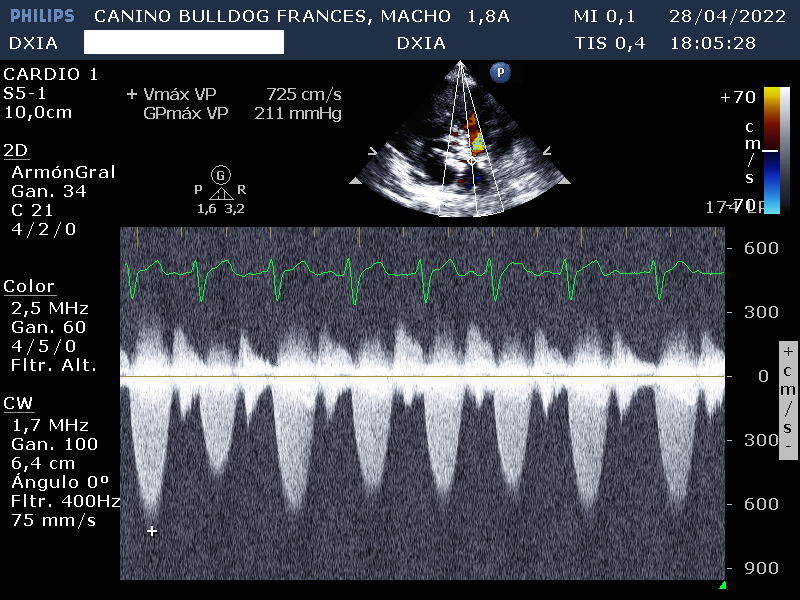

- Valvúla pulmonar: normoimplantada. Engrosamiento valvular con separación incompleta de las comisuras y dilatación post estenótica del tronco pulmonar. Gradiente de presión compatible con estenosis pulmonar severa. Movimiento paradójico del septo interventricular.

Por lo tanto el estudio ecocardiográfico es compatible con posible soplo de grado IV en el lado de derecho y displasia de la válvula tricúspide con dilatación severa de AD y VD. Además, presenta estenosis pulmonar severa con leve hipertrofia de la pared del VD.